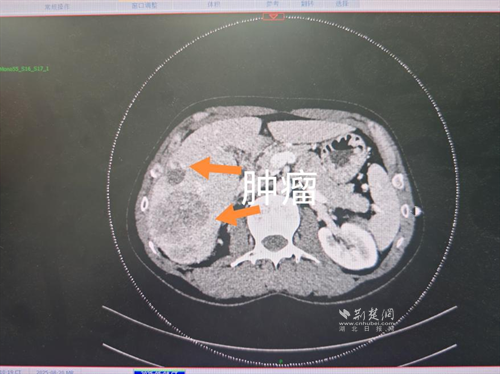

經(jīng)過肝膽外科牽頭組織的多學(xué)科MDT會診,團隊確認(rèn)其適合接受當(dāng)前國際先進的釔90樹脂微球選擇性內(nèi)放射治療。治療僅一個月后,患者病灶即從10cm縮小至6cm;術(shù)后六個月復(fù)查顯示,病灶體積進一步縮小近40%,影像學(xué)檢查提示完全緩解,臨床分期成功轉(zhuǎn)化,達到手術(shù)切除標(biāo)準(zhǔn)。